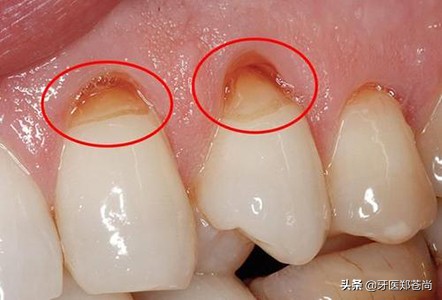

牙齿楔形缺损

牙齿楔形缺损,指的是牙齿颈部出现沟壑状的缺损,常常是连着好几颗牙齿,而出现这种形态缺损的原因,大多是因为个人刷牙不当,长期横向大力刷牙,长时间用磨损牙齿颈部造成的。

楔形缺损,不仅影响牙齿美观,更影响其正常使用,磨损后,吃饭嚼东西时,经常会感觉到牙齿敏感不适。磨损严重时,还得担心受怕,生怕哪天牙齿用着用着就突然折断了。